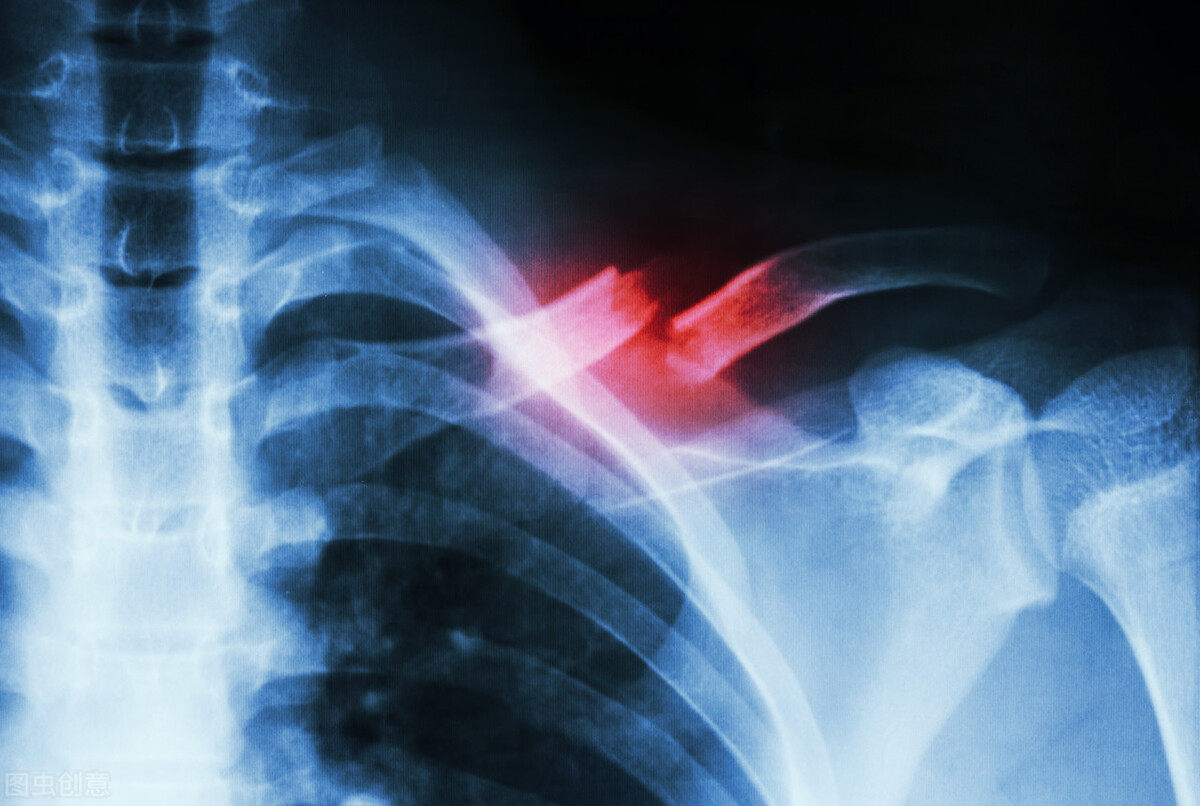

大部分人跑步时经历过胸痛,尤其是最近几年时有发生运动突发心脏病的时间,难免让人们担忧。跑步时剧烈胸痛不都是心脏病,也有可能是其他系统和器官障碍引起的。

一下子出现又突然消失的剧烈疼痛或来自于关节、肌肉或骨骼疼痛,如肋软骨炎。肋软骨炎可导致剧烈胸痛,胸部区域快速加压或突然运动时疼痛最为明显。疾病发作时呼吸都感觉到疼痛,有时疼痛会放射到肩膀和手臂。